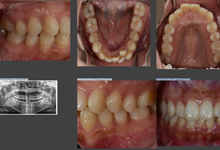

初診時には口腔内カメラを使用し、2回目以降もデータを積み重ねることで最適なプランを提案します。

初診ではまず患者さんの希望に沿って応急処置を行い、診断に必要なレントゲンと簡易的な口腔内写真、必要に応じて歯や歯茎の検査を行います。

2回目の診療

2回目の診療では基本的にお口の中の全体写真を取り、お掃除をさせてただいています。虫歯や歯周病は歯並びやかみ合わせの状態などのお口の中の環境が密接に影響してきます。そのため、なぜ虫歯になったか、歯周病が進行してしまったかについて理解していただくことが重要だと考えています。

この段階で患者さん個人個人にあった治療方針を提案させていただいています。